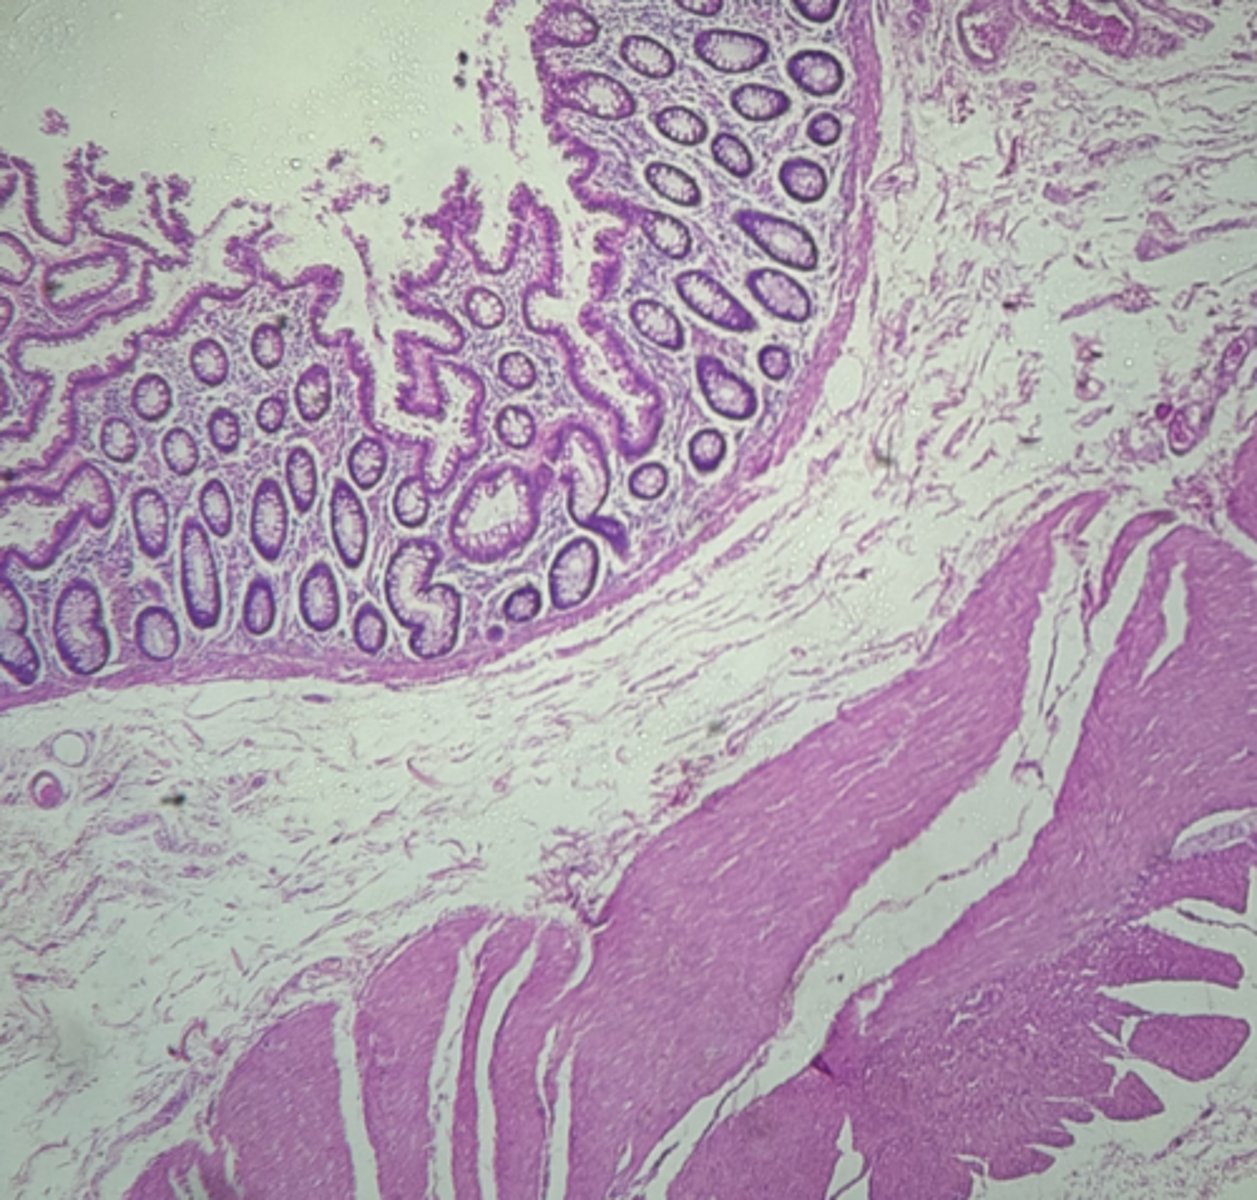

A- Esophagus

B- Stomach

Name the Tissue A & B

stomach

name the tissue

Esophagus